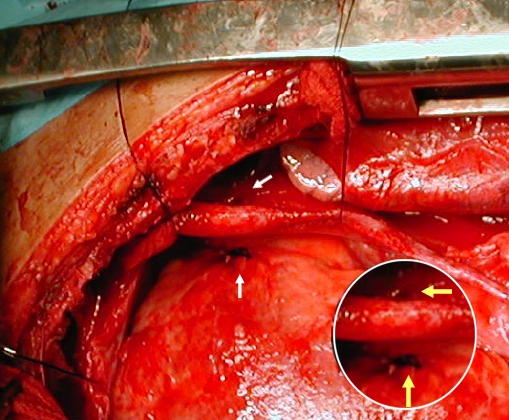

• Figura (1) :

Abordaje por esternotomía, pericardio vinoso distendido

Un pericardio distendido, tenso, que deja ver un contenido azulado oscuro (flechas).

La pleura derecha es abierta durante la disección pericárdica en sentido lateral, puede observarse el pulmón derecho expuesto.

•  Figura (2) :

El pericardio tomado entre pinzas y suspendido es escindido longitudinalmente emergiendo contenido hemático incoagulable y oscuro, 600 cc fueron drenados.

Pericardio escindido longitudinalmente drena el hemopericardio

• Figura (3) :

El pericardio una vez escindido longitudinalmente deja ver desde su cara interior la pequeña herida pericárdica (flecha amarilla) demostrando la penetración del arma punzo penetrante a la cavidad pericárdica.

• Figura (4) :

Fotográfica demostrando: (flechas blancas) La superior: el pequeño agujero en la cara externa pericárdica y de situación pleural derecha, aún permeable y responsable del hemotórax derecho.

La flecha blanca inferior: muestra el coágulo negruzco en la pared miocárdica ventricular derecha, motivo del  hemopericardio de lenta evolución por ser un sistema de baja presión y contenido por la bolsa pericárdica.

En Circulo blanco inferior derecho:

Un detalle en aumento de las lesiones encontradas.